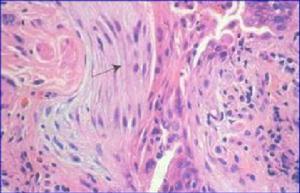

本病可廣泛累及胃腸道,可從咽至直腸,其中以胃和小腸受累最為常見,肝臟、大網膜等處亦可受到侵犯。鏡下可見大量嗜酸性粒細胞浸潤,可以聚積成堆,可累及為黏膜和黏膜下層,也可以某一層受累為主,最常見為黏膜和黏膜下層,其次為肌層,漿膜層最少見。Ⅰ型(嗜酸性胃腸炎) 為胃腸炎的特性類型。纖維胃鏡檢查,瀰漫型為黏膜充血、水腫、增厚,偶見表淺潰瘍糜爛,胃部病變酷似一般淺表性胃炎,活檢證實有大量嗜酸細胞浸潤。腸道病變多為瀰漫型,受累腸壁水腫、增厚、漿膜面失去光澤,有纖維素滲出物覆蓋。單腸性表一同多為胃或小腸的某一臟器病變。局限性者病變局限,發生於胃部者,病變往往在胃幽門或胃竇部。多腸性者,胃、十二指腸、小腸等處均有病變,往往為廣泛性、非延續性病變。

Ⅱ型(嗜酸性肉芽腫)本型少見。可在黏膜下形成單發或多發性腫物,往往出現幽門梗阻。以胃部(胃竇部)最為多見。且向周圍擴展生長,侵及迴腸、結腸處。為堅實或橡皮樣息肉狀腫塊、無蒂或有蒂凸入腔內,表面光滑,有黏膜覆蓋。